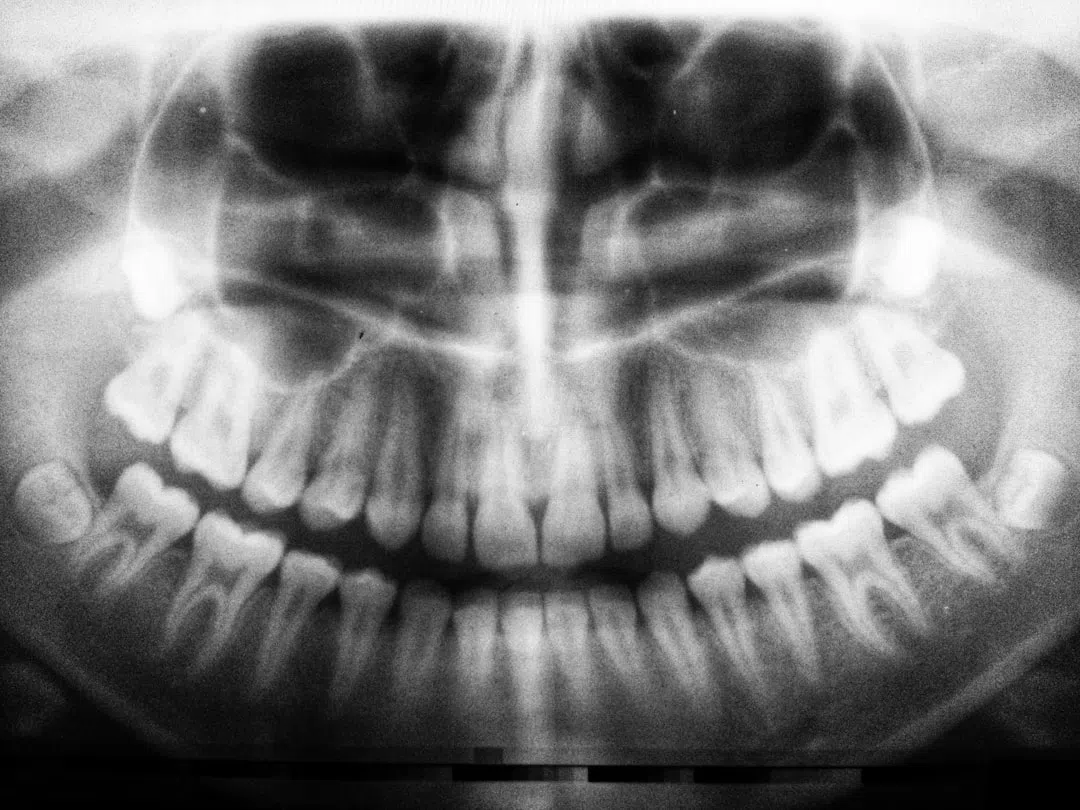

이번에 소개할 환자분의 케이스를 보면, 아래쪽에 뼈가 많이 녹아 있고 신경까지 가까운 상태입니다. 이 때문에 이를 빼면서 동시에 임플란트를 심는 것이 불가능한 위치입니다. 위쪽 치아도 빼야 하는 상황이었기 때문에, 기존 방법으로는 두 개의 임플란트를 심고 뼈 이식을 해야 했습니다. 이 과정은 최소 4개월에서 6개월이 걸리며, 전체 치료 기간은 거의 1년 가까이 됩니다.

디지털 기술을 활용하여 어려운 위치에 임플란트를 심지 않고, 비교적 쉬운 위치에 임플란트를 계획할 수 있습니다. 이렇게 하면 뼈 이식이 필요 없고, 임플란트 개수는 그대로 두 개지만 치아는 세 개가 되는 효과를 볼 수 있습니다.

이 새로운 방식으로 치료한 결과, 치료 기간은 3개월이 채 되지 않았으며, 비용도 절감되었습니다. 기존의 어려운 위치에서 벗어나 비교적 쉬운 위치에 임플란트를 심고, 뼈 이식 없이 치아 세 개를 만드는 데 성공했습니다.